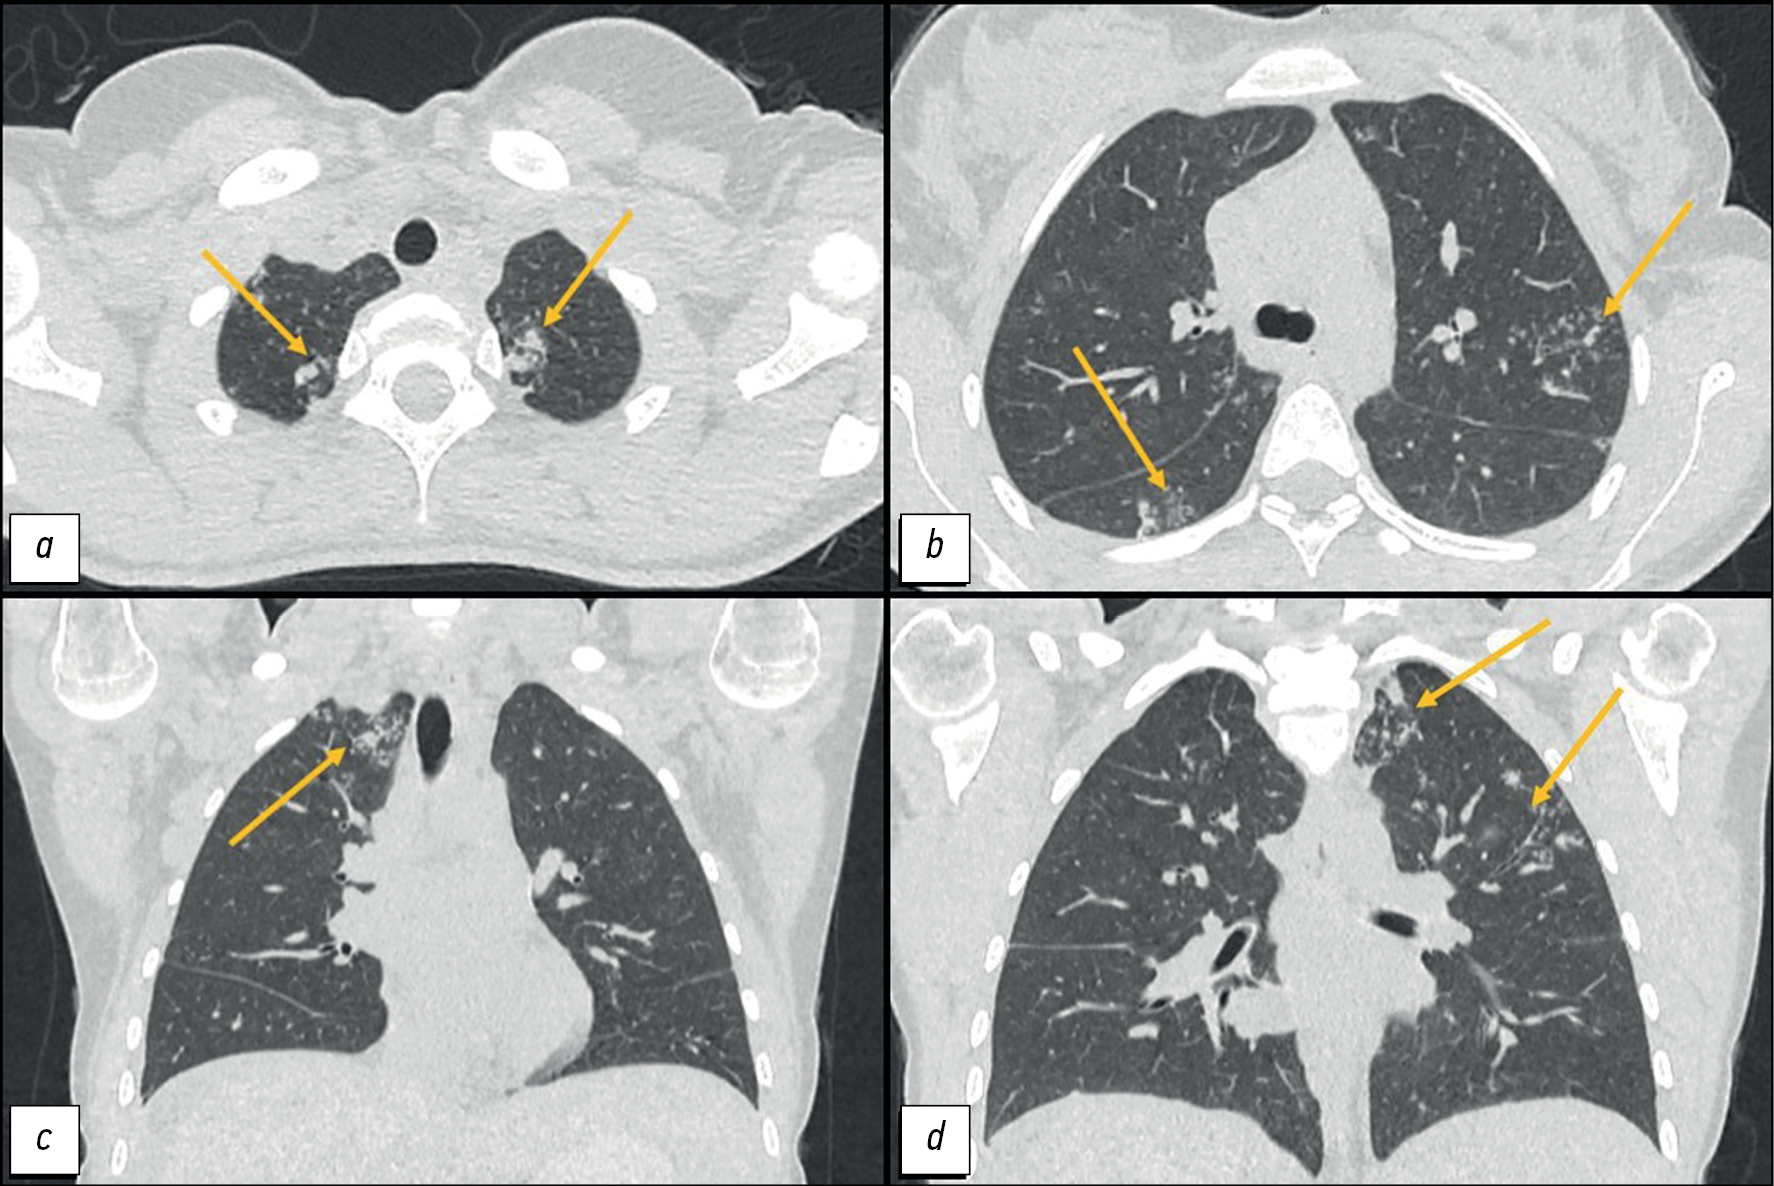

The differential diagnosis between peritoneal tuberculosis and peritoneal carcinomatosis is quite challenging because of the similarity of the clinical picture and laboratory and instrumental examination data. Peritoneal tuberculosis and peritoneal carcinomatosis may present with the development of ascites, lymph nodes, and intestinal loop conglomerates. This article presents the clinical case of a young patient who, after her second childbirth, noted the appearance of intense pain in the neck and between the scapulae. Two months later, she experienced pneumonia with a positive reaction to antibiotic therapy. After another 2 months, she experienced recurrent ascites and gastrointestinal symptoms for the first time. The examination revealed ovarian masses and signs of peritoneal carcinomatosis and lung nodules. However, the clinical presentation was atypical for peritoneal carcinomatosis, and lung lesions were suspicious for tuberculosis, which allowed us to hypothesize the presence of tuberculosis of multiple localizations. The diagnosis was confirmed by laparoscopy with a biopsy of the involved tissues and subsequent histological and laboratory confirmation of the etiological role of Mycobacterium tuberculosis. The described case demonstrates the importance of using all available diagnostic methods to establish the causes of ascites in young female patients for differential diagnosis between specific and neoplastic etiologies.